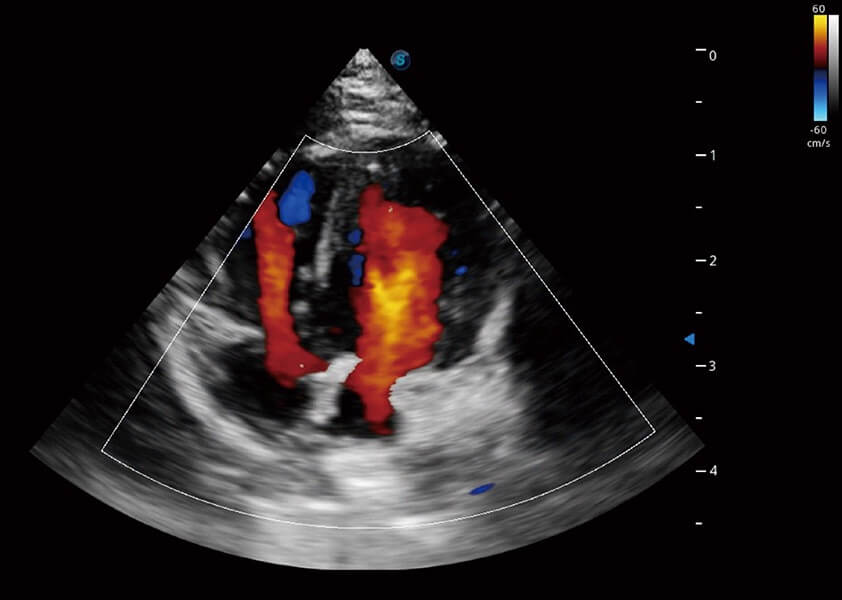

心脏解决方案

ProPet 60 配备了丰富的心脏探头群、先进的成像技术和专业的心脏测量工具,可帮助动物医生为不同体型和生理结构的动物提供心脏和心肌功能的全面评估。

• TDI 组织多普勒成像

实时用颜色表示心肌组织运动,观察和定量组织的运动情况,对快速检测与评估心肌的灌注和活性、电传导及心肌收缩和舒张功能等均能提供重要的诊断信息。

• MQA 心肌定量分析

通过心肌识别技术与二维斑点追踪技术相结合,对心脏的超声图像进行量化分析。计算心肌17个节段的应变、应变率、速度、位移等,并通过牛眼图的形式进行呈现。

• AMM 解剖M型

通过360度任意调节3条M型取样线,在同一心动周期上观察心脏不同位置的运动曲线,得到准确的心功能测量数据,有效评估心肌运动及左心室功能。

(犬)四腔心血流